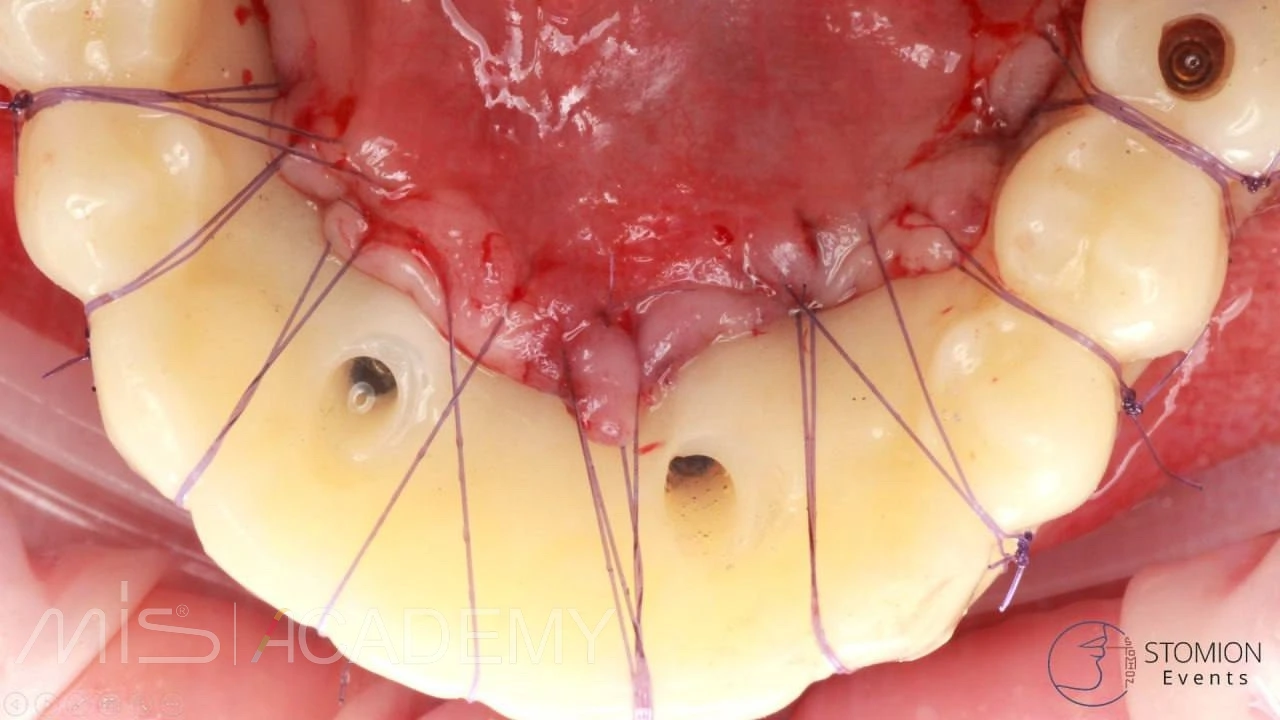

Выполнено:

— Multifix на 4-х MIS C1.

— Коннекты во фронте.

— 30 градусов МЮ дистально.

— Мягкотканная пластика + B2S в критических зонах вестибулярно.

— Навигация полнопротокольная, разборная, накостная.

— Нагрузка немедленная, внутриротовая сварка.